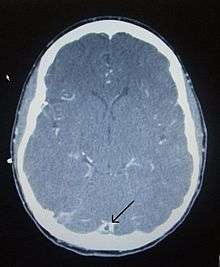

There are various neuroimaging investigations that may detect cerebral sinus thrombosis. Cerebral edema and venous infarction may be apparent on any modality, but for the detection of the thrombus itself, the most commonly used tests are computed tomography (CT) and magnetic resonance imaging (MRI), both using various types of radiocontrast to perform a venogram and visualise the veins around the brain.[1]

Magnetic resonance venography employs the same principles, but uses MRI as a scanning modality. MRI has the advantage of being better at detecting damage to the brain itself as a result of the increased pressure on the obstructed veins, but it is not readily available in many hospitals and the interpretation may be difficult.[5]